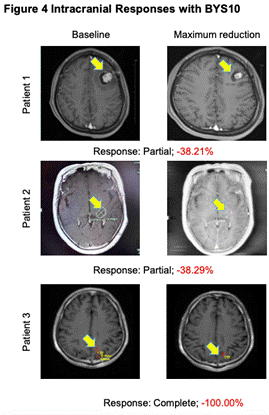

з ”з©¶иҒҢе‘ҳеңЁ4дҫӢиҮіе°‘жңү1дёӘеҸҜдёҲйҮҸйў…еҶ…з—…зҒ¶пјҲ1дҫӢйў…еҶ…е®Ңе…Ёзј“и§Јпјүзҡ„жӮЈиҖ…дёӯи§ҶеҜҹеҲ°йў…еҶ…жҠ—иӮҝзҳӨжҙ»жҖ§�гҖӮгҖӮгҖӮгҖӮ�гҖӮ

еӣҫ4.йў…еҶ…жҠ—иӮҝзҳӨжҙ»жҖ§